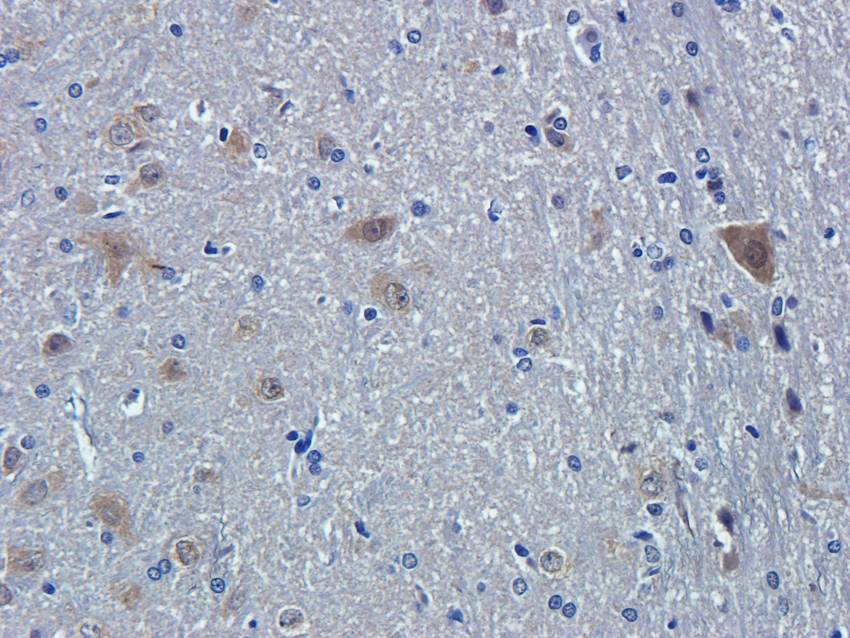

100 μg - PGP9.5 antibody [orb6713]Featured

ELISA, ICC, IF, IHC-P, WB

Human, Mouse, Rat

Rabbit

Polyclonal

Unconjugated

100 μg - FOXP3 antibody [orb34127]Featured